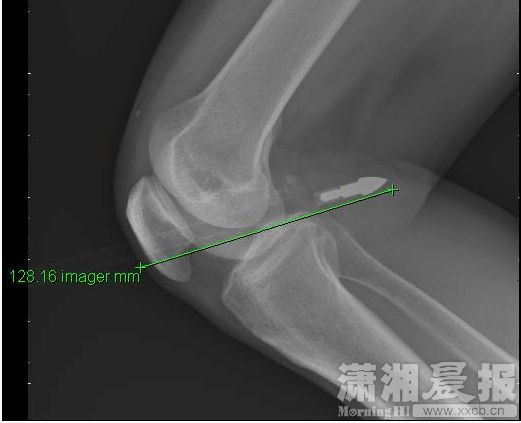

An X-ray shows Wang's injured knee. [Photo/xxcb.cn] |

No one likes to be caught off guard. A 51-year-old man was shot by an arrow at his right knee while he was hanging clothes at the balcony of his home in Changsha, Hunan province, xxcb.cn, a local news portal reported.

It turned out it was Liang, a neighbor of Wang, who was responsible for the whole thing. Liang was practicing arrow shooting, about 50-meter away at the garden of the community compound, when the arrow went loose.